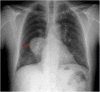

Hydatid cyst caused by the larval form of Echinococcus is a worldwide zoonosis. The lungs and liver are the most common sites involved. While the lung parenchyma is the most common site within the thorax, it may develop in any extrapulmonary region including the pleural cavity, fissures, mediastinum, heart, vascular structures, chest wall, and diaphragm. Imaging plays a pivotal role not only in the diagnosis of hydatid cyst, but also in the visualization of the extent of involvement and complications. The aim of this pictorial review was to comprehensively describe the imaging findings of thoracic hydatid cyst including pulmonary and very unusual extrapulmonary involvements. An outline is also given for the findings of complications and differential diagnosis of thoracic hydatid cyst.